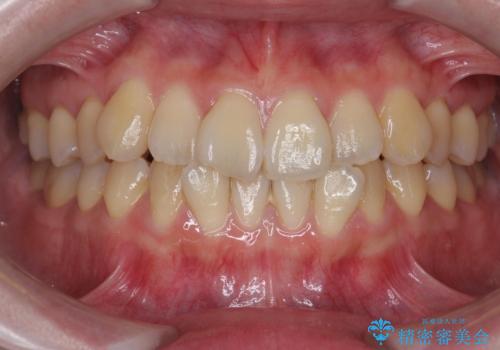

前歯のねじれ・ガタガタを10か月で改善!20代女性の矯正治療|クリアブラケットでむし歯になりにくい歯並びへ改善

担当医 齋藤佑磨

前歯のねじれ 矯正治療による歯並び改善